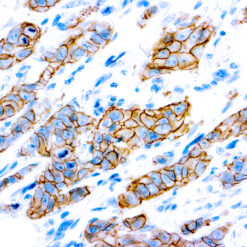

Cytokeratin (CAM5.2)

Anti-Cytokeratin (CAM 5.2) reagent has a primary reactivity with human keratin proteins that correspond to Moll’s peptides #7 and #8, Mr 48 and 52 kilodaltons (kd), respectively. Cytokeratin 7 and 8 are present on secretory epithelia of normal human tissue but not onstratified squamous epithelium. Anti-Cytokeratin (CAM 5.2) stains most epithelial-derived tissue, including liver, renal tubular epithelium, and hepatocellular and renal cell carcinomas. Anti-Cytokeratin (CAM 5.2) might not react with some squamous cell carcinomas.

| Positive Control Tissue | Colon, Lung, prostate and breast tissue. |